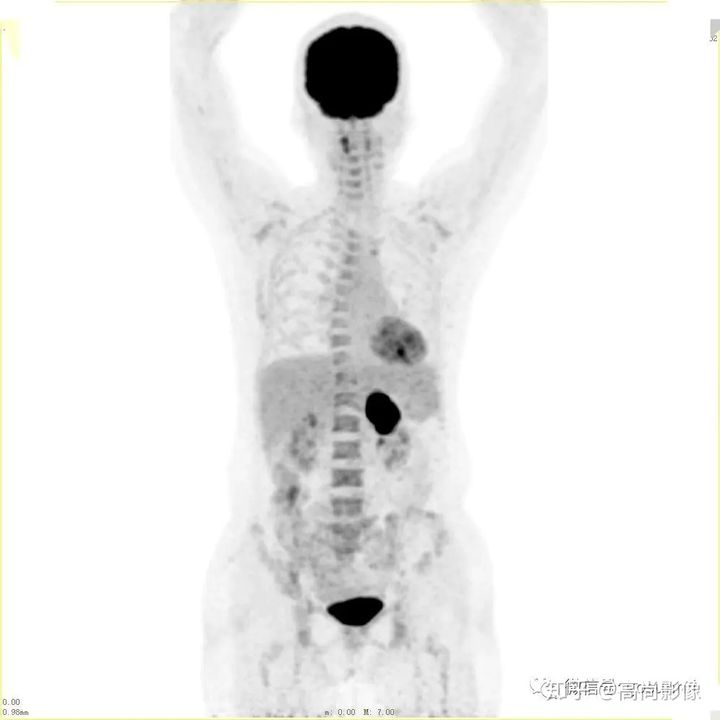

肺癌化療前評估的MIP圖

(最大密度投影圖)

肺癌化療后評估的MIP圖